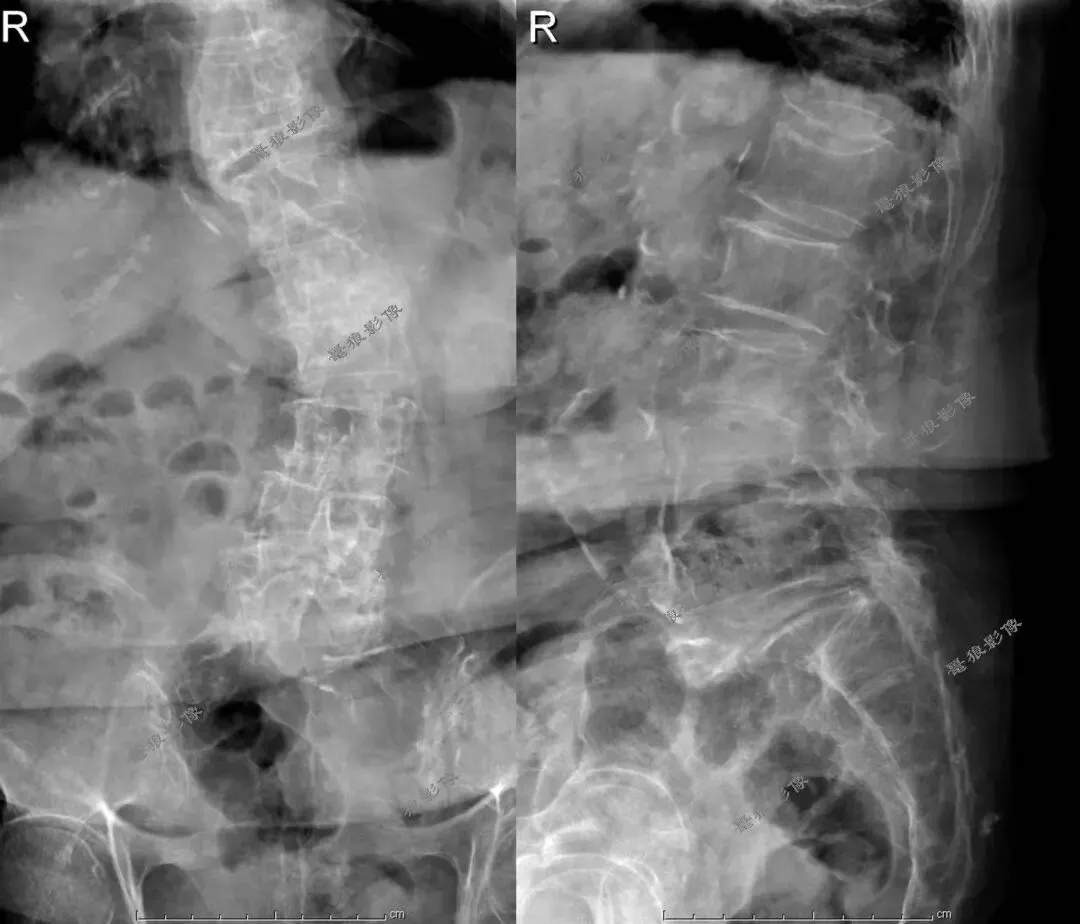

三、腰椎平片(术后)